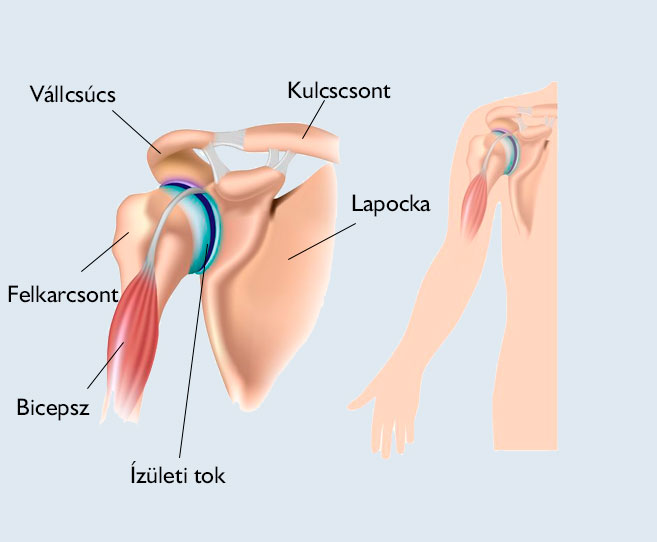

A kezelés végezhető a térden, bokán, csípőn, vállon is. Az eddigi eredmények kimagasló javulást mutatnak a tünetek enyhülésében, a fájdalom csökkenésében, és ennek következtében bizonyos esetekben a protézis beültetés elkerülhető. Ez a könnyen kezelhető rendszer arra lett kifejlesztve, hogy a zsírszöveteket kinyerjék, akár 20 perc alatt feldolgozzák és ugyanazon sebészi eljáráson belül vissza is ültessék a kezelésre szoruló területbe.